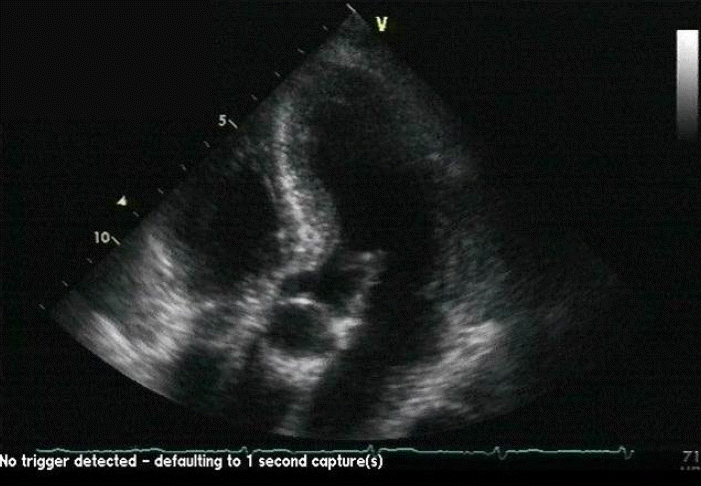

Figure 4.

Echocardiography shows mildly thickened left and right ventricles, with a sparkling pattern, strongly suggesting cardiac amyloidosis.